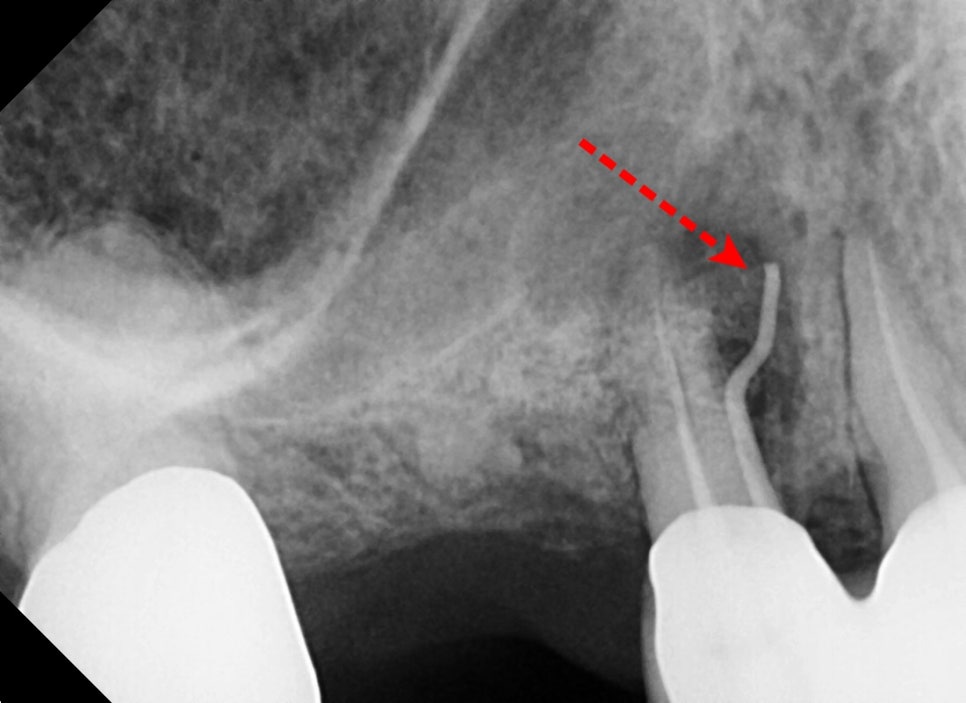

염증이 어느 치아에서 시작되는지 검사를 통해 알아냈습니다.

고리를 거는 힘을 받는 앞 치아 뿌리 쪽에 염증이 생기고

그 염증이 잇몸 바깥으로 염증 주머니를 만들어서 불편감을 일으키고 있었습니다.

틀니의 거는 힘에 의해 앞 치아가 반복적으로

무리한 힘을 견뎌 녀는 과정에서 뿌리의 흡수와 염증반응이 생긴 것입니다.

치료해 주셨던 원장님께서도

치아를 살리기 위해 치근단절제술이라는

뿌리의 문제 부분을 제거하고 뼈이식을 통해 회복을 지켜보자고 하셨고

저 역시 수술하신지 얼마 안 되어 소독하며 지켜보았지만

뼈이식 재료의 염증반응과 치아 통증으로 인해 발치가 불가피했습니다.